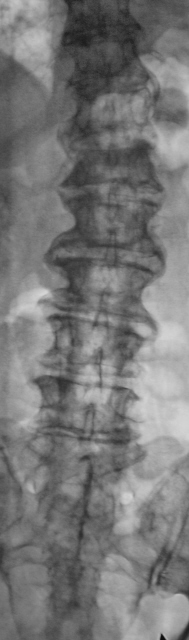

Позвонили из хирургического отделения, чтобы на передвижном аппарате (предназначен только для снятия конечностей) произвели рентгенограммы "грудного отдела позвоночника". Так как, что-то не нравится неврологу. Пациент находится в отделение с диагнозом "Кишечное кровотечение"...

Коллегам было разъяснено "где зад, а где перед", а также для чего нужен передвижной аппарат, и с учетом состояния пациента было предложено доставить в рентгеновский кабинет для полноценного рентгенологического исследования. С пациентом поговорил что болит и когда заболело. Пациент (весьма преклонного возраста мужчина) поведал, что месяц тому упал, и потом отказали ноги. произвели исследование - рентгенографию, "подключили" линейную томографию.

L1 сломал недавно, а L4 - давно

Да. Л1, по всей видимости, и сломали 1 месяц тому.

перелом Л1. Деформирующий спондилёз поясничного отдела позвоночника.